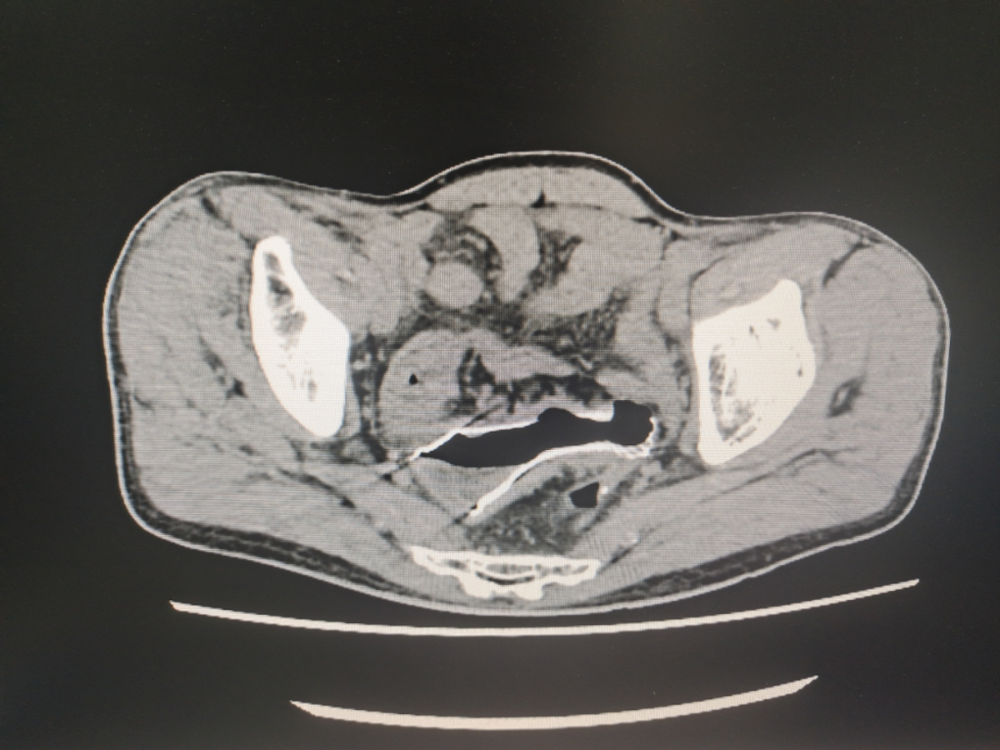

病例(lì)資料:患者,劉某某,男,73歲,因大便未解6天入院,伴有腹部脹痛(tòng),無嘔吐。入院查體;心(xīn)肺無異常、腹彭隆、壓(yā)痛、叩診呈鼓音(yīn),入院後急診腹部(bù)CT提示(shì)。乙狀結腸占位(wèi)並腸道梗阻(zǔ),急診腸鏡示:直乙交界新生物並腸道狹窄。患者於2023年11月(yuè)20日在介入室行腸鏡下腸道支架置入(rù)術,術中腸道流出糞水,術後第一天患者無腹痛(tòng)、腹脹,肛門恢複排便排氣,後複查CT示(shì)腸腔(qiāng)積(jī)氣積(jī)液明顯好轉,臨床療(liáo)效顯著。

(左)支架置入前(qián)CT

(右)支架置入後CT